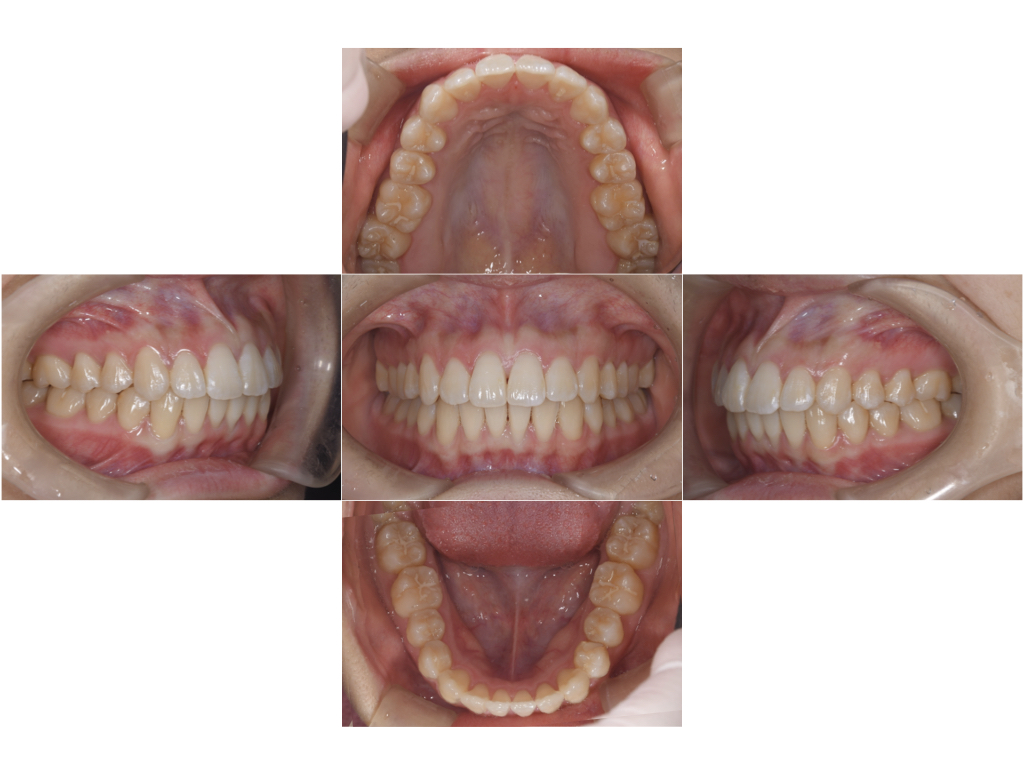

年齢 20歳

性別 女性

初診日 2022年9月

主訴 歯並びを治したい

治療内容 マウスピース矯正

治療期間 4ヶ月

治療費用 50万円

治療経過 歯並びを治したいとのことで来院された。

特に前歯の前突を治したいとのことだった。

本来の適応症は抜歯矯正も視野に入れた全顎矯正ではあったが、治療期間と費用を十分相談の上、マウスピースによる部分矯正で対応することになった。

口腔内スキャナーのiTeroを用いてシミュレーションを行い、矯正後のイメージを実際に見ていただいた上で、インビザラインにて矯正治療を行なった。

実質動的期間は14週でシミュレーション通りに終了し、仕上がりにも大変満足していただいた。